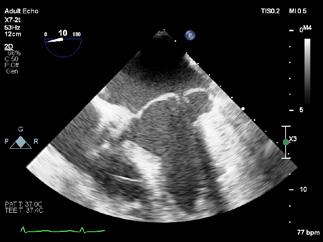

Cazuri disperate în chirurgia cardiacă –atunci când abordul minim invaziv este soluția

Dr. Ion Iovu, Prof. Univ. Dr. Lucian Dorobanțu, Dr. Andreea Bogdan, Dr. Ioana Băjenaru, Dr. Oana Ioniță, Dr. Mădălina Cojocaru, Dr. Toma Iosifescu, Conf. Dr. Cătălin Badiu, Dr. Alexandru Vasilescu